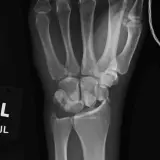

Over 2,100 interactive radiology cases, curated by radiologists for your level of training. Scroll, window, and view cases full screen — just like on PACS. Click linked findings in each writeup to jump straight to them on the image. Cases include sample reports, a focused discussion section, original illustrations, and videos.

完全交互式病例,配备您在 PACS 上期待的各项工具——滚动、调窗、缩放、平移、测量、ROI 和全屏模式。

丰富的标注直接在病例图像上突出关键发现。点击病例讲解中的关联发现,即可跳转至其在扫描上的精确位置。